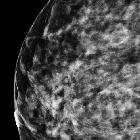

Nicht-Komedo duktales in situ Karzinom der Mamma

Non-comedo type ductal carcinoma in situ is a subgroup of ductal carcinoma in situ (DCIS). This group comprises of relatively less aggressive types with low nuclear grade. It has multiple patterns which are often mixed: